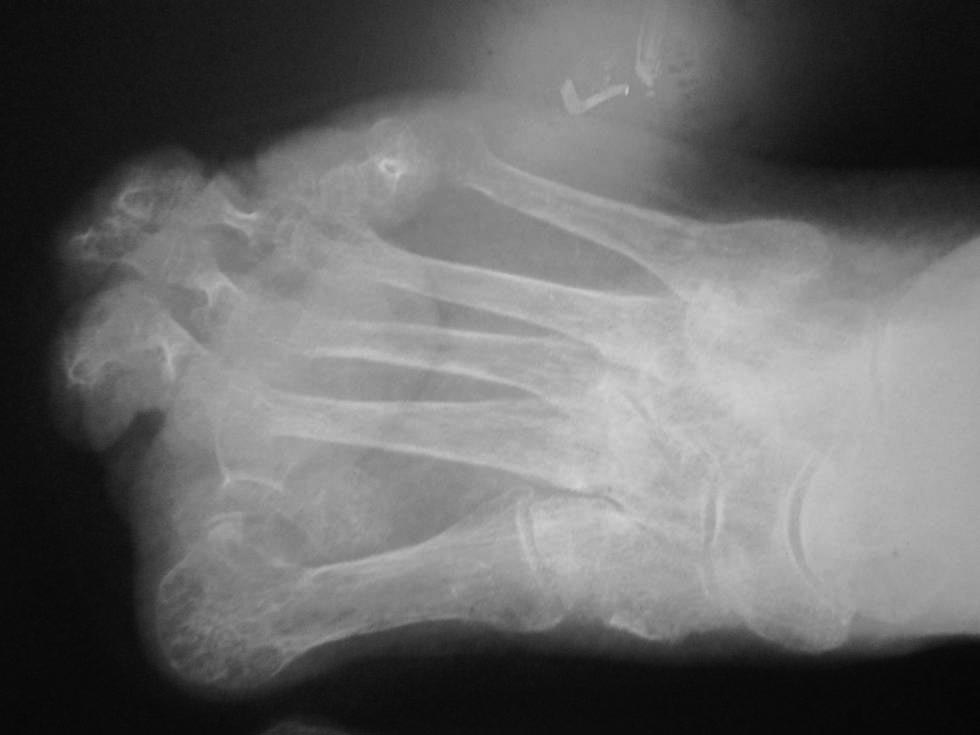

[Ortho] Hallux abductovalgus

рентген